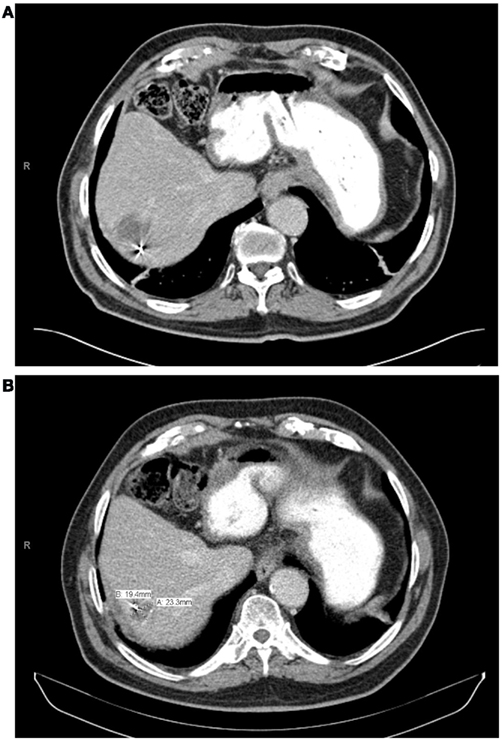

With a median follow-up of 21 months, the median survival was 16.1 months and the 2 year actuarial overall survival was 25.7%. Of the lesions with evaluable post-treatment radiographic imaging, eight had stable disease (80%), and two had progressive disease (20%) at first imaging follow-up. An example of treatment response as determined by CT scan is demonstrated in Figure 4. None of these patients had a complete or partial response. One year Kaplan–Meier estimate of local control was 72%, and only three lesions demonstrated radiographic evidence of local failure at last follow-up. On univariate analysis, the only factor associated with local failure was initial RECIST response to SBRT (p = 0.0047). None of the remaining factors, including BED10, conformality index, prescription isodose line, and location within the liver were statistically significantly associated with local failure.

FIGURE 4

www.frontiersin.org

Figure 4. (A) One month post-treatment CT scan, (B) 10 month post-treatment CT scan.